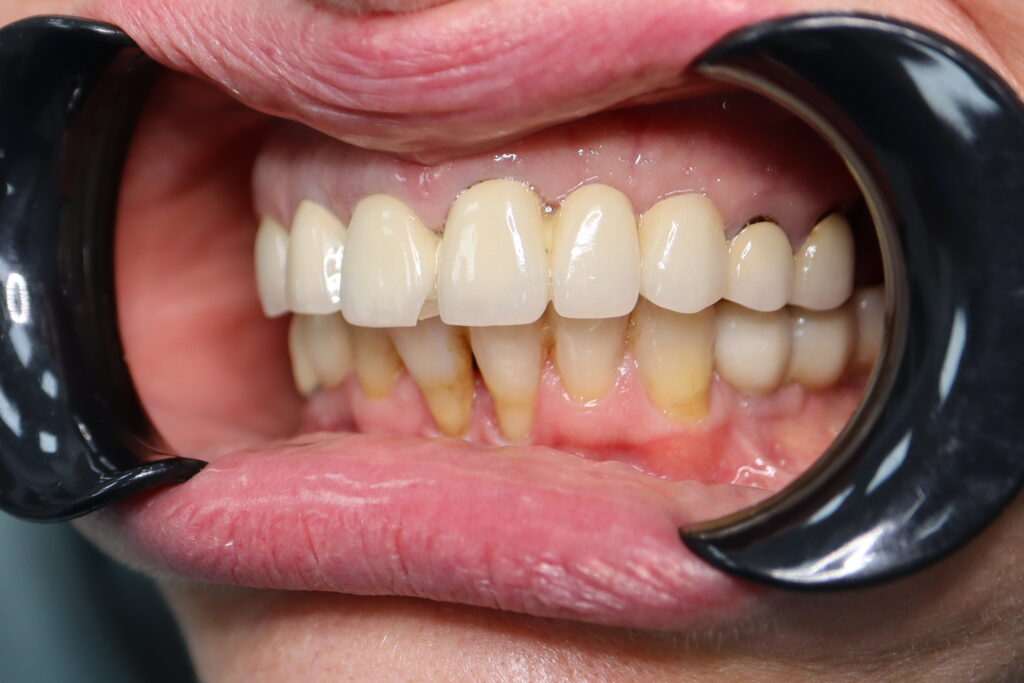

Результаты

Стоимость всего комплекса: 5300 USD (цена указана ориентировочно по курсу НБРБ на день оплаты)

результат имплантации